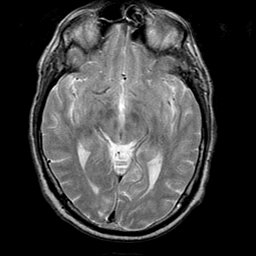

Meningioma, MR Study #1 -- Slice #8

[Home][Help][Clinical] Slice 8